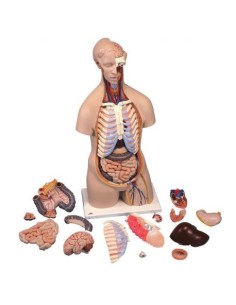

Scopri il Mondo dell’Anatomia con Modelli anatomici di Precisione

Modelli Anatomici Dettagliati per Ogni Necessità

Dal cranio in 22 parti con incastri magnetici ai modelli di colonna vertebrale, da quelli di articolazioni a quelli di cuore, ogni pezzo della nostra collezione è progettato per un’immersione totale nello studio dell’anatomia umana. I nostri modelli, realizzati tramite scansioni di ossa vere, garantiscono un’esperienza tattile autentica e una fedeltà di peso quasi identica agli originali.

Strumenti Didattici Innovativi per l’Educazione e la Pratica Medica

Essenziali per studenti e professionisti, i nostri modelli anatomici sono strumenti didattici che permettono di osservare le strutture anatomiche con precisione, eliminando la necessità di dissezioni o studi invasivi. Sono inoltre utili per spiegare ai pazienti le patologie, rendendo la comunicazione più efficace e risparmiando tempo prezioso.